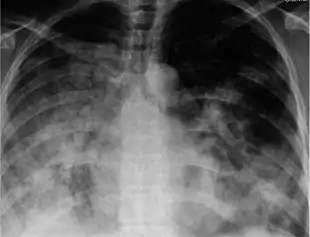

Symptomatic infections are usually mild and limited to the upper respiratory tract, but progression to pneumonia is relatively common. Pneumonia may be caused by the primary viral infection or by a secondary bacterial infection. Primary pneumonia is characterized by rapid progression of fever, cough, labored breathing, and low oxygen levels that cause bluish skin. It is especially common among those who have an underlying cardiovascular disease such as rheumatic heart disease. Secondary pneumonia typically has a period of improvement in symptoms for 1–3 weeks[13] followed by recurrent fever, sputum production, and fluid buildup in the lungs,[1] but can also occur just a few days after influenza symptoms appear.[13] About a third of primary pneumonia cases are followed by secondary pneumonia, which is most frequently caused by the bacteria Streptococcus pneumoniae and Staphylococcus aureus.[8][1]